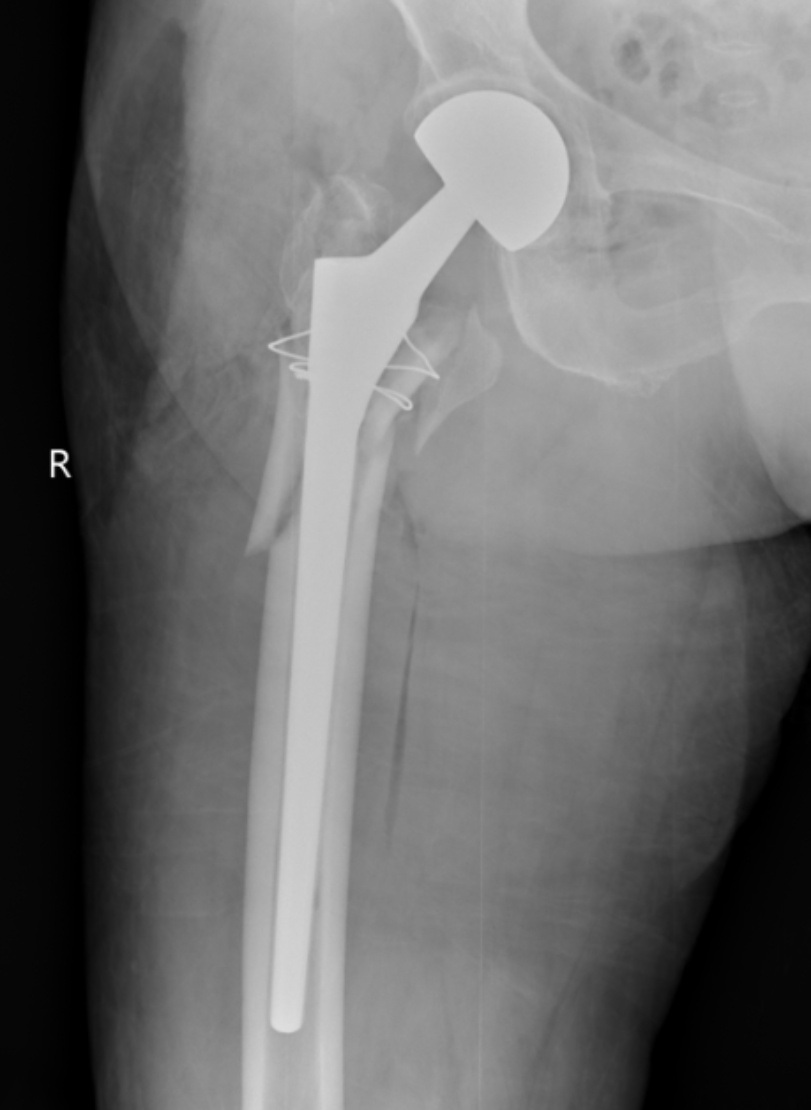

典型病例影像学表现见图1~10。图1为86岁女性右侧股骨转子间骨折(Evans Ⅲ型)患者,术前X线示骨折断端部分错位,术后X线示骨折位置可以及假体位置良好;图2显示了一名81岁男性患者,诊断为左侧股骨转子间骨折,类型为Evans V型,合并股骨干陈旧性骨折。患者接受了生物型加长柄半髋关节置换手术,并进行了股骨近端的钢丝捆扎内固定。术后X线示假体位置良好,股骨近端予钢丝捆扎固定;图3为87岁女性左侧股骨转子间骨折(Evans V型)患者,术后X线示假体位置良好,股骨大小转子骨折位置可,钢丝捆扎固定在位有效;图4为75岁女性左侧股骨转子间骨折(Evans V型)患者,术前X线示左侧股骨转子间骨折PFNA术后、骨折未愈合、内固定断裂。术后假体匹配良好,股骨近端钢丝内固定稳定可靠;图5为75岁男性左侧股骨转子间骨折(Evans IV型)患者,术后股骨大转子出现轻度位移,假体位置正常。图6为87岁男性左侧股骨转子间骨折(Evans V型)患者,给予DAA入路加长柄半髋关节置换,术前X线片,清晰地显示出左侧股骨转子间的骨折情况,术后X线影像,显示股骨的大小转子骨折位置良好,钢丝内固定装置在位稳定,假体位置良好;图7为77岁女性右侧股骨转子间骨折(Evans V型)患者,术前X线片显示右侧股骨转子间存在骨折且股骨大小转子均有累及和移位,术后X线片显示股骨小转子轻度移位,内固定装置位置稳定,假体位置良好;图8为70岁男性左侧股骨转子间骨折(Evans III型)患者,术前的X线片,清晰地显示了左侧股骨转子间的骨折情况,股骨近端髓腔钙化灶,术后假体位置满意;图9为77岁女性右侧股骨转子间骨折(Evans V型)患者,术前X线片,显示右侧股骨转子间及转子下部位骨折情况。术后假体匹配良好;图10为71岁男性右侧股骨颈骨折(Evans IV型)患者,术前X线片,显示右股骨转子间骨折的情况;术后X线表明股骨的大转子和小转子骨折位置保持良好,内固定装置稳固,术后假体位置正常。

(a) (b)

Figure 4. A 75-year-old female patient with left intertrochanteric fracture of the femur (Evans V type). (a) Before surgery; (b) After surgery

4. 75岁女性左侧股骨转子间骨折(Evans V型)患者。(a) 术前;(b) 术后